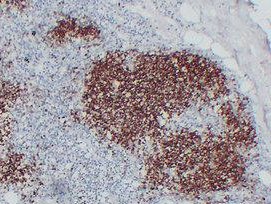

CD1a

CDla是一种转移膜蛋白,分子量为43~49kDa,在B淋巴细胞、树突细胞、皮质胸腺细胞、抗原提呈细胞、胃肠道上皮细胞等表达阳性。CDla 可用于胸腺皮质肿瘤的标记、皮肤B细胞淋巴瘤的辅助诊断、胸腺癌和肺肿癌的辅助区分等,联用S100 可用于朗格汉斯组织细胞增生症的诊断与鉴别。